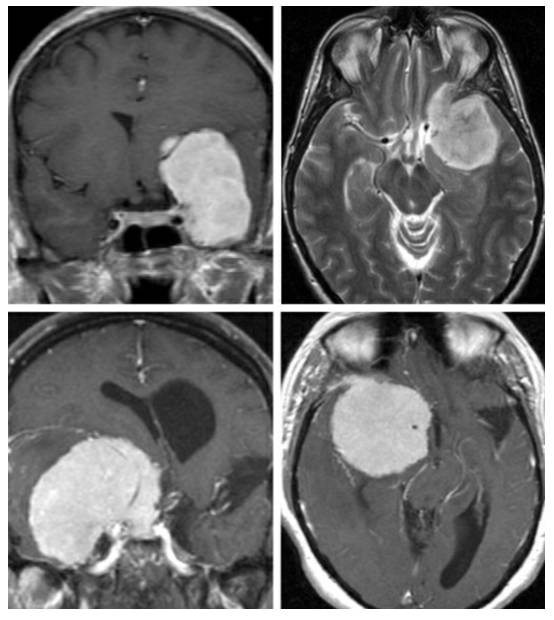

图2. 根据蝶骨嵴内侧型脑膜瘤是否侵犯内侧神经血管和包绕颈动脉穿支血管,可表现出不同的手术难度。上图所示为一例向内侧轻度延伸的脑膜瘤,侧裂大脑中动脉分支覆盖在肿瘤的上极。下图所示为一例真正意义上的蝶骨嵴/床突内侧型脑膜瘤,向内侧显著生长并包绕ICA。

图3. 一例第三组或右侧视神经孔脑膜瘤。肿块所处的关键位置导致相对快速的视力恶化,使得肿瘤在早期得以发现。

图4. 冠状位和轴位图片显示蝶骨嵴中部/内侧脑膜瘤与周围血管结构之间的典型关系。往往可发现更为明显的视器受压的证据。

该患者因右侧视力减退就诊,诊断为巨大的蝶骨嵴内侧型脑膜瘤。

图18. 第一行MRI显示肿瘤的位置和眶顶骨质增厚。硬膜外切除床突,早期对视神经进行减压。游离并保护MCA远端分支(第二行)。逐步向颅底解剖,将肿瘤沿着ICA分离出来,这样有助于松动肿瘤组织(最后一行,左图)。在视神经孔远端找到视神经,通过切除管内肿瘤组织,将神经游离出来(最后一行,右图)。